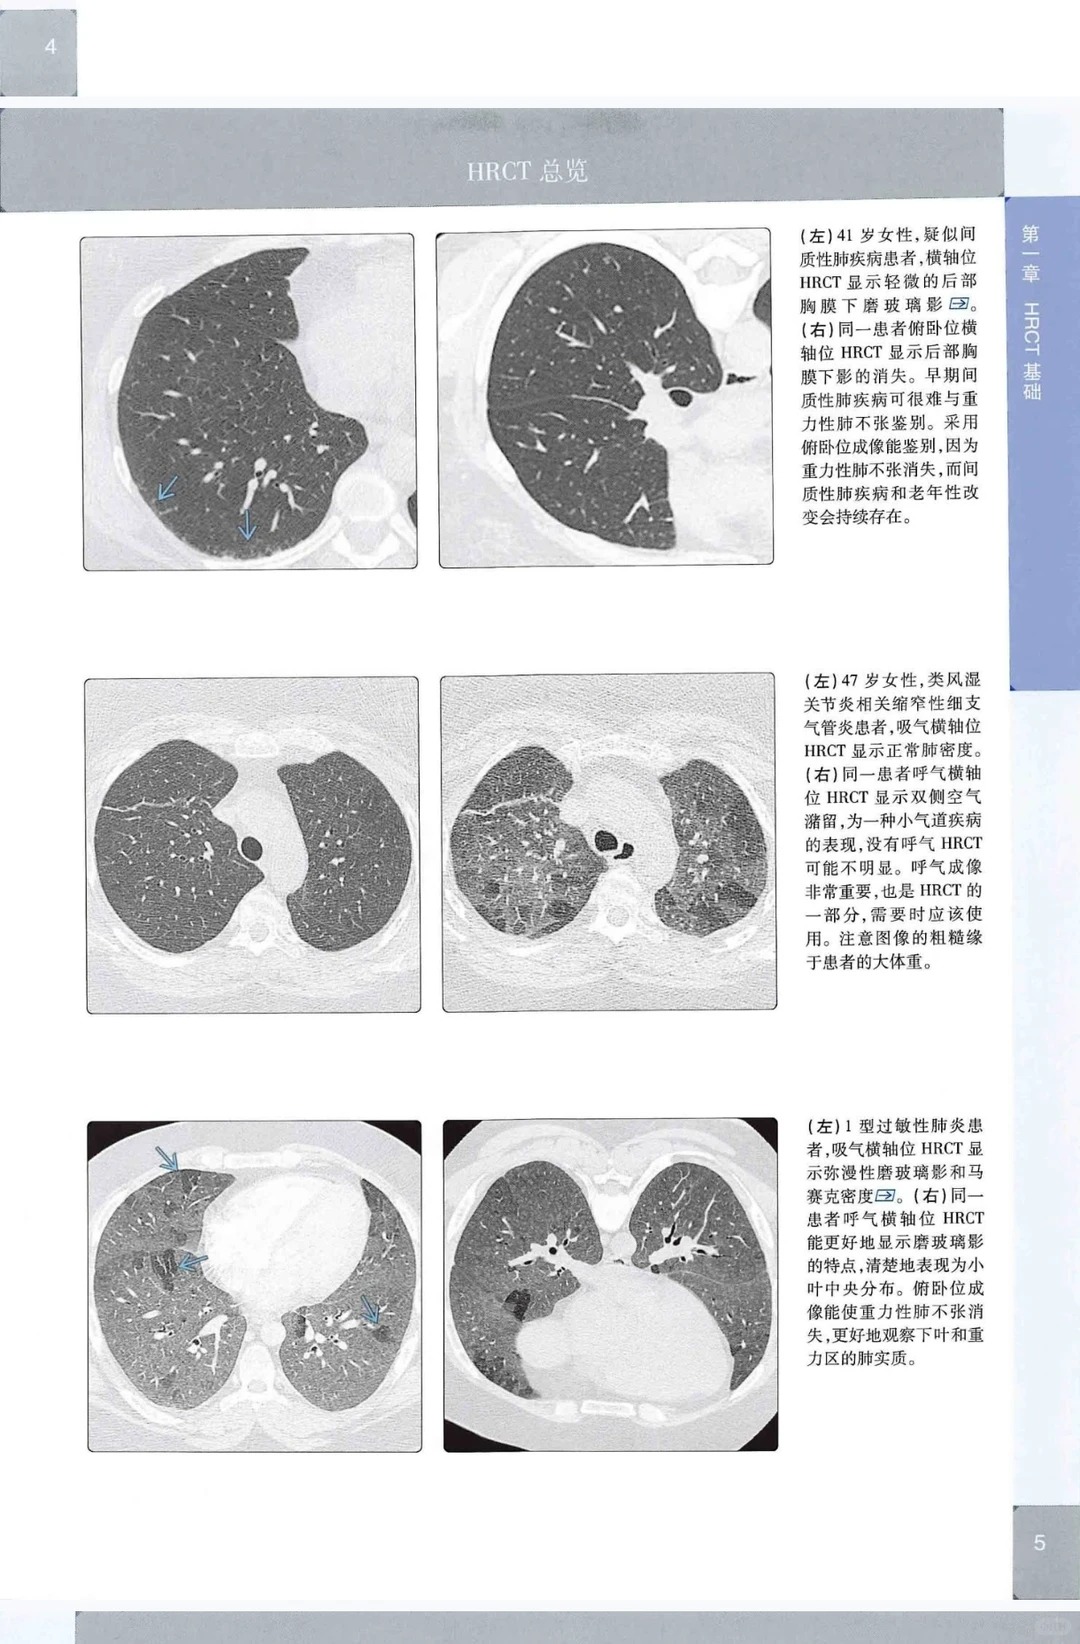

1. 超高清图像升级,细节拉满 对比第1版,图片质量肉眼可见提升,超高清影像精准呈现肺部病灶细节、纹理结构,小病灶、细微纹理也能清晰识别,告别模糊不清的困扰,看图学习、临床读片效率直接翻倍,助力精准读片。

3. 双维度讲解,结构清晰 采用“疾病分类+影像模式”双维度讲解,既按感染、肿瘤、间质病、气道病等疾病类型展开,也按网格、结节、实变等影像模式梳理,结构清晰、层次分明,查漏补缺超方便,提升学习与读片效率。